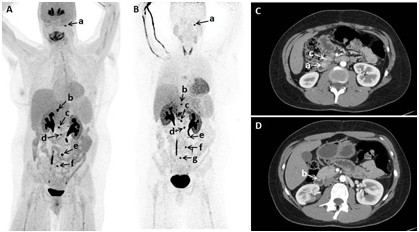

Functional and anatomic imaging; (A, B) 18F-fluorodopa positron emission tomography (PET)/computed tomography (CT) showing multiple tumors in a patient; (C, D) Early arterial phase of axial CT of abdomen performed with negative enteric contrast showing small masses in another patient.